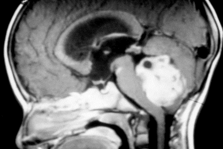

MRI showing human medulloblastoma tumor growing in the cerebellum (white ball at right)

The problem: most of the drugs we use to treat medulloblastoma are 30 years old. In the past 5 years we have learned a lot in the laboratory about different subtypes of medulloblastoma (there are at least 4 - and probably 6 - subtypes). But while we have learned more about what makes these cancer cells grow, we are lacking new therapies that we can use to kill cancer cells. In particular, we need drugs that will work on the worst prognosis subtypes.

Our goal: To develop new, less toxic therapies for patients with aggressive medulloblastoma. We set out to find drugs that would kill cells that had activation of a gene called MYC. The two worst subtypes of medulloblastoma have high levels of this gene, indicating they may be sensitive to drugs that target MYC.

Our progress: Targeting the “Achilles’ Heels” of MYC-driven medulloblastoma. One of the ways that MYC makes cancer cells grow more is by changing their metabolism. This may also represent an Achilles’ heel for these cancers. There are drugs that specifically target the metabolic changes downstream of MYC. The good news is that these drugs don’t appear to harm the normal brain or even baby brain cells. Some of these drugs were tried years ago in children in clinical trials, but they were never extensively tested in MYC-driven cancers. We have found that these drugs not only kill medulloblastoma cells in a dish, but that they can cause regression of advanced medulloblastoma tumors growing in mice. With a little more pre-clinical testing, we hope to move this drug into clinical trials for children with MYC-expressing medulloblastoma.